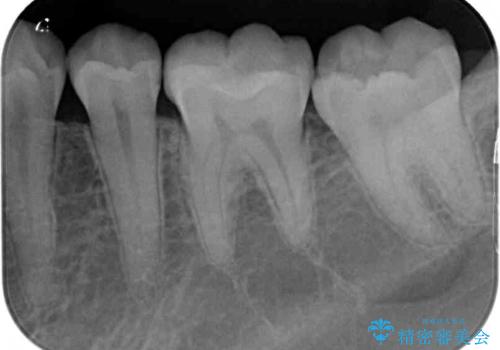

セラミックとゴールド 奥歯のむし歯治療

- 奥歯の銀歯と虫歯を気にして来院された患者様です。

下顎は口を開けたときに目立つためセラミックインレーに、上顎奥歯は機能面を優先してゴールドインレーにて修復治療を行うこととしました。